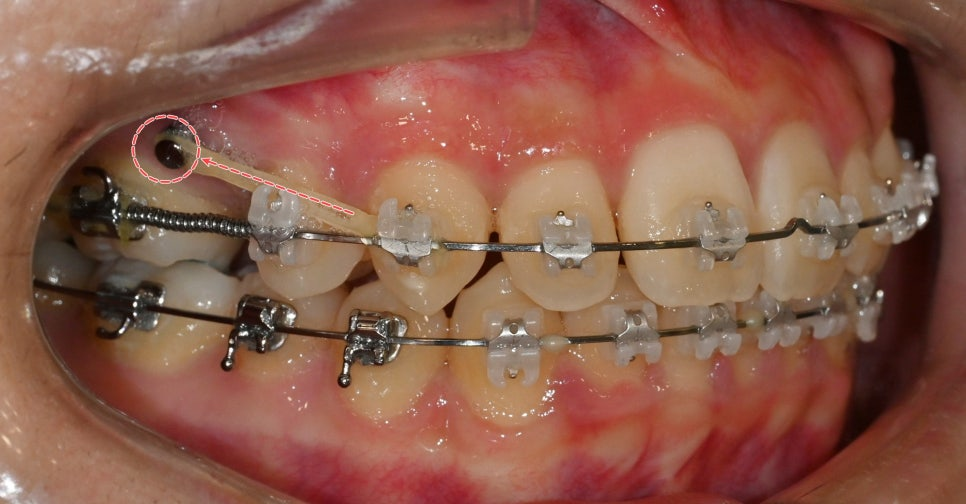

23.09.08

이소맹출된 오른쪽 위 작은 어금니 하나를

제외한 자연치 겉면에

클리피씨 브라켓을 부착했습니다.

삐뚤 빼뚤한 치열을

1차로 배열합니다.

이후 미니 스크류를 식립하여

오픈 코일 스프링으로 인해

오른쪽 전치부의 치열이

이동되지 않도록 고정합니다.